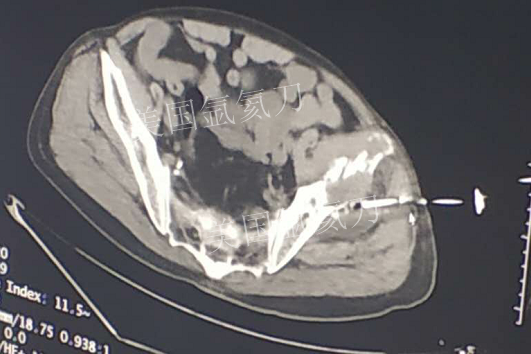

73岁臀部氩氦刀冷冻消融